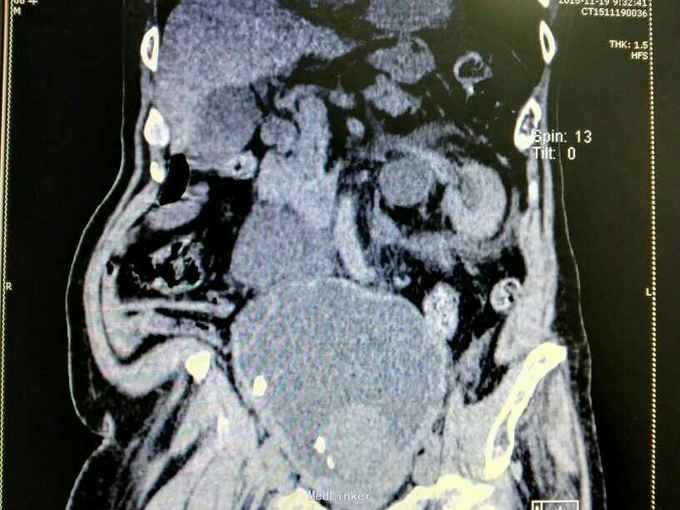

男性,87岁,进行性排尿困难10年,小便不能自解2天入院。无血尿,无发热、腰痛。一直口服藏药治疗前列腺增生症。既往无高血压、糖尿病。

腹部明显膨隆。耻骨上膀胱区扣浊。肾区无扣痛。尿常规少许白细胞。肌酐506,电解质正常。Hb116。

前列腺增生症 尿潴留 双肾积水 肾功能不全,膀胱结石,尿路感染,双肾多发囊肿。给予留置导尿,间断分次放尿后,出现肉眼血尿,持续膀胱冲洗,颜色较红,伴血凝块间断堵管。